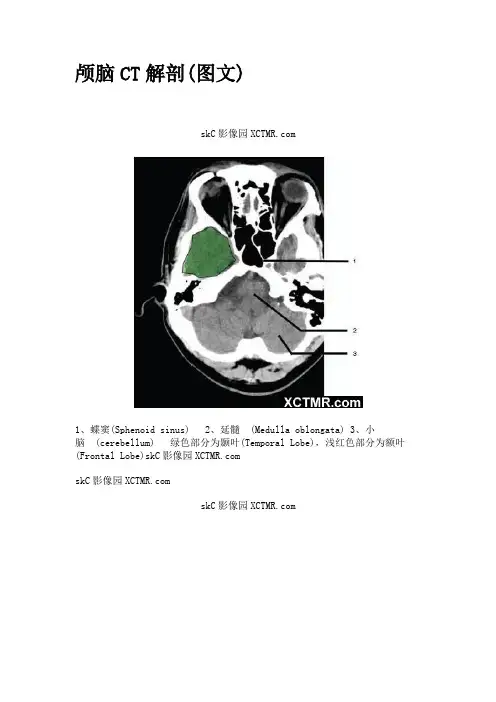

颅脑CT解剖(图文)skC影像园1、蝶窦(Sphenoid sinus)2、延髓(Medulla oblongata)3、小脑(cerebellum) 绿色部分为颞叶(Temporal Lobe),浅红色部分为额叶(Frontal Lobe)skC影像园skC影像园skC影像园4、第四脑室(Fourth ventricle)5、小脑中角(Middle cerebellar peduncle)6、乙状窦(Sigmoid sinus)7、颞骨及乳突气房 (Petrous temporal bone and mastoid air cells) 8、桥小脑角(Cerebellopontine angle) 9、脑桥(Pons) 10、垂体窝(Pituitary fossa) 绿色部分为颞叶(Temporal Lobe),浅红色部分为额叶(Frontal Lobe)skC影像园skC影像园11、小脑蚓部(Cerebellar vermis) 12、基底动脉(Basilarartery) 13、桥前池(Prepontine cistern) 14、鞍背(Dorsum sellae) 15、侧脑室颞角(Temporal horn of lateral ventricle) 绿色部分为颞叶(Temporal Lobe),浅红色部分为额叶(Frontal Lobe)skC影像园skC影像园16、环池(Ambient cistern) 17、角间池(Interpeduncular cistern) 18、大脑角(Cerebral peduncle) 19、侧裂池(Sylvian fissure) 绿色部分为颞叶(Temporal Lobe),浅红色部分为额叶(Frontal Lobe) skC影像园skC影像园20、小脑上池 (Third ventricle) 21、侧脑室前角 (Frontal horn of lateral ventricle) 21a、第三脑室(Thirdventricle) 绿色部分为颞叶(Temporal Lobe),浅红色部分为额叶(Frontal Lobe),黄色部分为枕叶(Occipital Lobe)skC影像园skC影像园22、尾状核头部 (Head of caudate nucleus) 23、岛叶 (Insular cortex) 24、外囊(External capsule) 25、豆状核(Lentiform nucleus) 26、丘脑(Thalamus) 绿色部分为颞叶(Temporal Lobe),浅红色部分为额叶(Frontal Lobe),黄色部分为枕叶(Occipital Lobe)skC影像园skC影像园27、纵裂(Interhemispheric fissure) 28、内囊前肢(Anterior limb of internal capsule) 29、内囊膝部(Genu of internal capsule) 30、内囊后肢(Posterior limb of internal capsule) 31、侧脑室三角区及脉络丛钙化(Trigone of lateral ventricle and calcified choroid plexus) 32、侧脑室枕角(Occipital horn of lateral ventricle) 绿色部分为颞叶(Temporal Lobe),浅红色部分为额叶(Frontal Lobe),黄色部分为枕叶(Occipital Lobe),褐色部分为顶叶(Parietal Lobe)skC影像园skC影像园33、侧脑室体部(Body of lateral ventricle) 34、放射冠(Corona radiata) 浅红色部分为额叶(Frontal Lobe),黄色部分为枕叶(Occipital Lobe),褐色部分为顶叶(Parietal Lobe)skC影像园skC影像园35、半卵圆中心(Centrum semiovale) 浅红色部分为额叶(Frontal Lobe),黄色部分为枕叶(Occipital Lobe),褐色部分为顶叶(Parietal Lobe) 额骨(FB— Frontal bone) 顶骨(PB — Parietal bone) 枕骨(OB— Occipital bone)skC影像园skC影像园36、中央前回(Pre-central gyrus) 37、中央沟(Centralsulcus ) 38、中央后回(Post-central gyrus) 浅红色部分为额叶(Frontal Lobe),褐色部分为顶叶(Parietal Lobe)skC影像园skC影像园浅红色部分为额叶(Frontal Lobe),褐色部分为顶叶(Parietal Lobe)skC影像园skC影像园浅红色部分为额叶(Frontal Lobe),褐色部分为顶叶(Parietal Lobe)skC影像园。